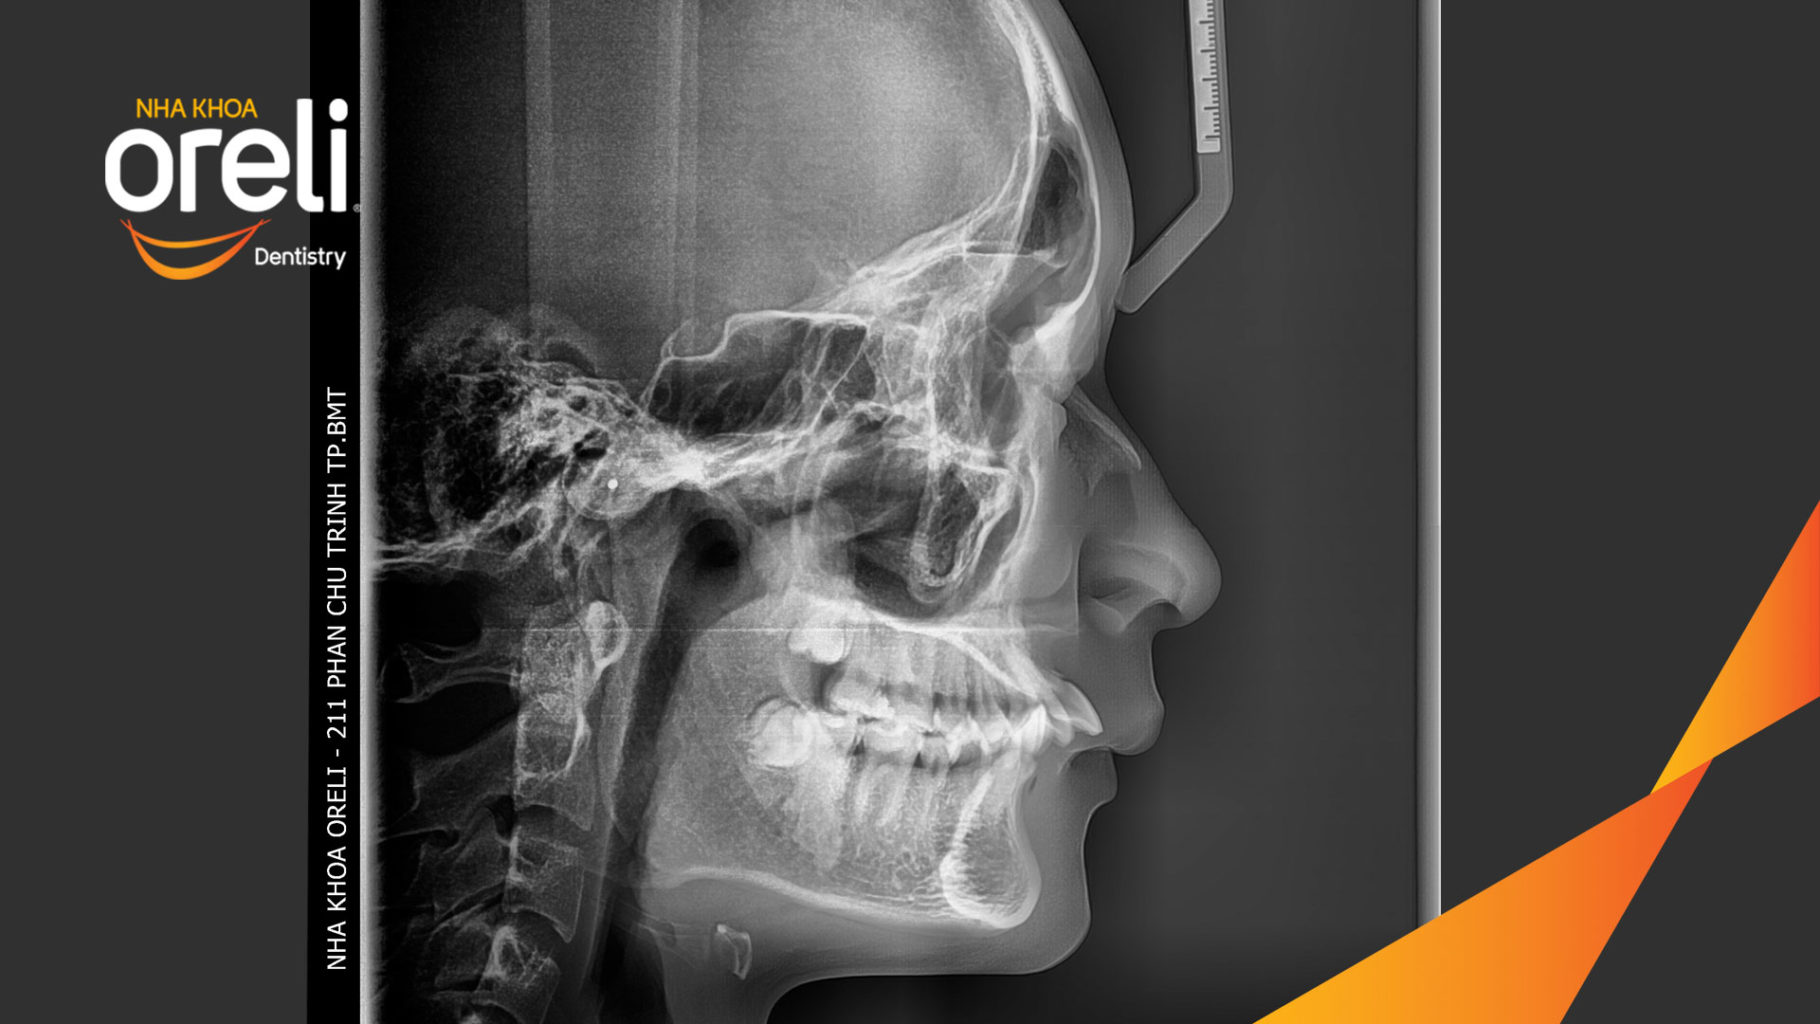

Giải pháp: làm đều chỉnh khớp cắn sâu không nhổ răng

Kết quả: khớp cắn đúng, cằm tiến ra trước với mặt nghiêng đẹp

Hình ảnh thực tế